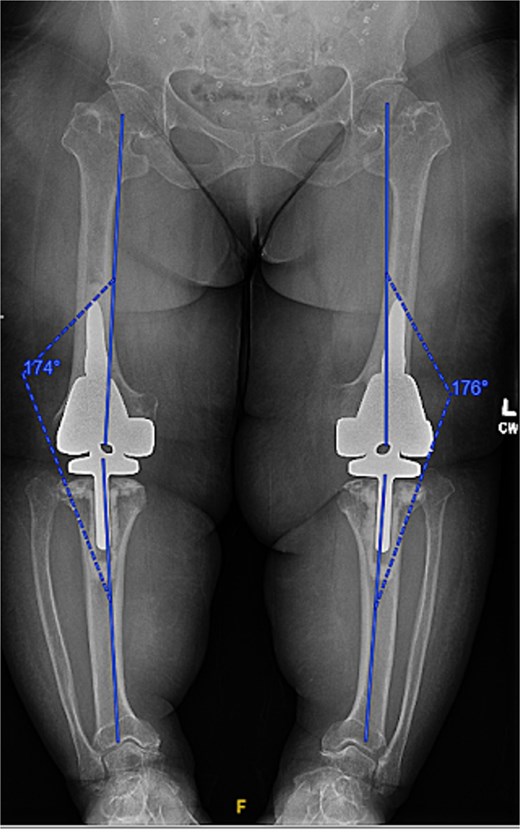

At the 2-year follow-up, the patient reported no significant pain, demonstrated a normal gait, and had active bilateral knee range of motion from 0° to 125°. There was no joint line tenderness or instability. Surveillance radiographs confirmed well-aligned and stable components with no evidence of implant failure or periprosthetic lucency (Fig. 3). At the five-year follow-up, the patient remained very satisfied with her knees and denied knee pain. On exam, her gait was slightly antalgic, but active bilateral knee range of motion remained preserved at 0° to 120°, and both knees remained stable throughout range of motion and nontender to palpation. Radiographs continued to show stable prosthetic components without evidence of implant failure or periprosthetic lucency (Fig. 4).

Five-year postoperative AP radiographs showing continued stability of bilateral rotating-hinge implants with maintained alignment and no radiographic evidence of implant failure.